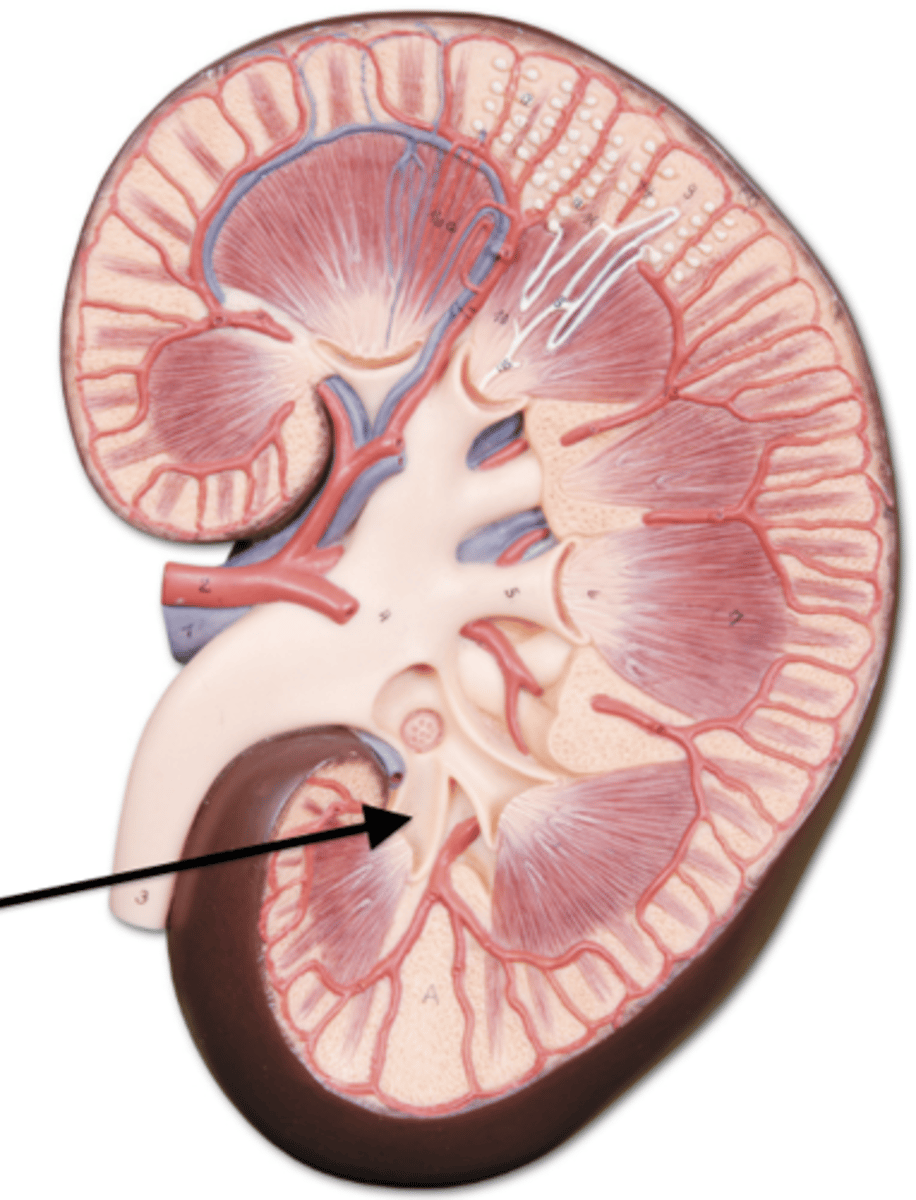

kidney

fibrous capsule

outer covering

renal cortex

renal medulla

renal papilla

major calyx

minor calyx

renal pelvis

renal pyramids

renal columns

renal artery

renal vein